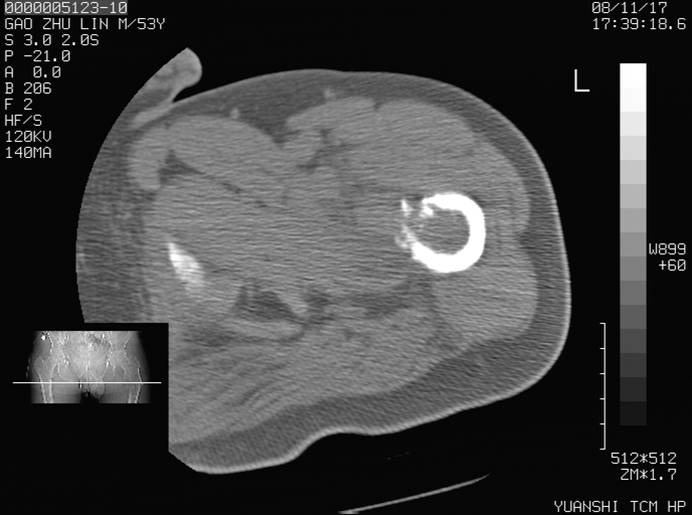

标题: CT16696:M53Y,左股骨上段骨折。 [打印本页]

标题: CT16696:M53Y,左股骨上段骨折。

左股骨上段外伤1个小时,左股骨上段疼痛。村医以腰椎间盘病变给以按摩及理疗数天。

图像不太清楚,左股骨上段外伤性骨折?病理性骨折?

左股骨上段粉碎性骨折

左股骨上段粉碎性骨折;建议上传骨窗看看是不是病理性的啊!

左股骨上段粉碎性骨折,不排除病理性骨折可能。

考虑骨肉瘤伴病理骨折

考虑:骨肉瘤伴病理骨折.

病理性骨折,考虑转移所致.